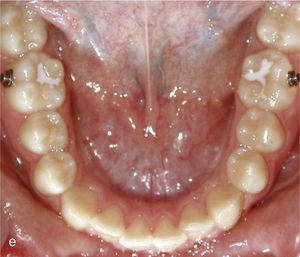

EspaciosEl cierre de espacios en el sector anterior se clasifica dentro de los movimientos dentales sencillos con el sistema Invisalign. En la vista intraoral de la figura 6a se observan sendos sectores anteriores con espacios en maxilar y mandíbula. Se realizó el cierre de los espacios y también la intrusión de los dientes 11 y 21. Con dicho fin fueron adheridos ataches rectangulares en los dientes 13, 23, 11 y 21. La imagen intraoral de la figura 6b muestra el resultado del tratamiento después de cerrar los espacios y de reducir la sobremordida vertical.

Vista intraoral de los dientes anteriores separados entre sí y de los ataches en los dientes 13, 11, 21 y 23 para el cierre de los espacios y también en los dientes inferiores 33, 34, 35, 43, 44 y 45 para obtener el anclaje necesario para la intrusión de los dientes anteroinferiores (a). Vista intraoral del resultado después del cierre de espacios y de la creación de una sobremordida horizontal y vertical fisiológica (b).